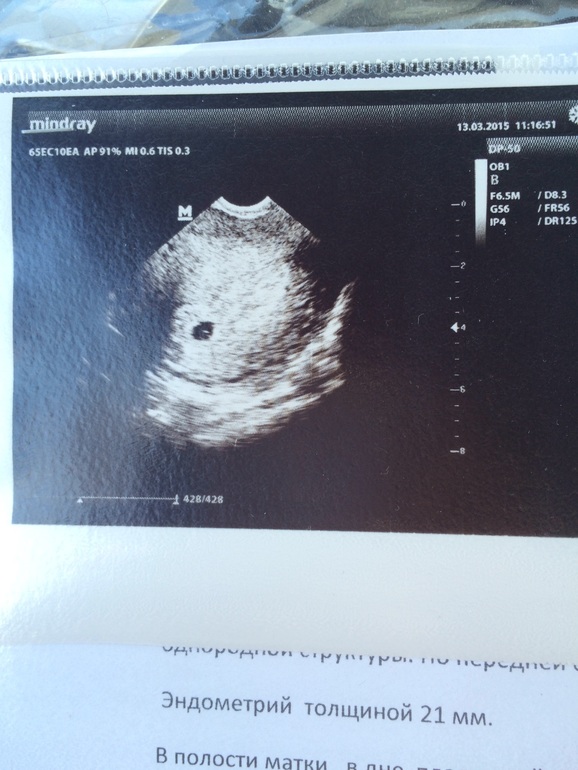

Нас наконец увидели😄но не услышали😔

Сходила на очередное УЗИ.